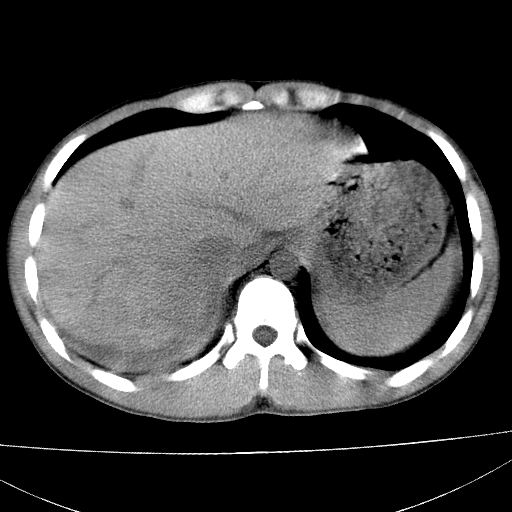

肝脏及肾脏明显有损伤性改变并激发腹腔内积液(血),以肝脏撕裂及肾周积血显著。

1)肝破裂伴腹腔积液(血)。2)右肾破裂伴右肾包膜下及肾周血肿。3)腹部空腔脏器穿孔可能。4)右侧少量胸腔积液(血)。

肝肾挫裂伤,右肾周及包膜下血肿,腹腔积液,不排除空腔脏器穿孔,建议行增强检查

肝、右肾包膜下血肿,右侧腰大肌及腹膜后血肿;腹腔少量积血;腹腔疑有少量游离气体伴肠破裂。

肝右叶及右肾均见挫伤破裂出血。

1肝挫伤伴腹腔积液。2右肾挫裂伤伴右肾包膜及肾后间隙肿血肿。3右肾脏周围的积气,十二指肠显示结构不清,考虑十二指肠降部破裂可能性大。